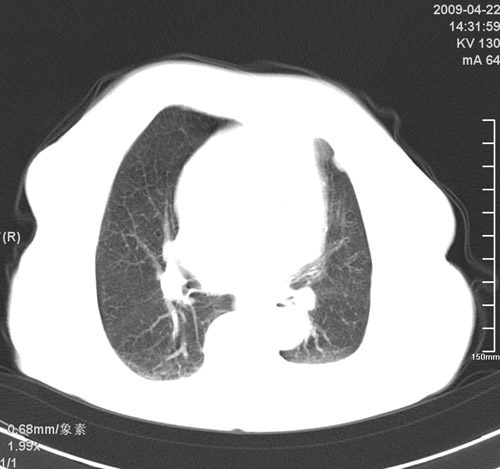

以下是引用杀毒软件在2009-4-22 18:45:00的发言:[br]考虑----左肺感染性病变〔真菌可能性大〕-----建议痰检。